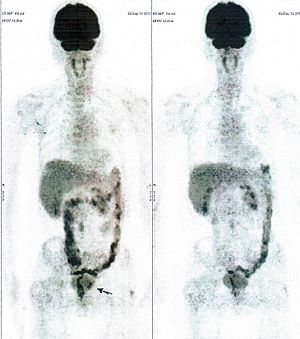

CASE NO: 12 (ENDOMETRIAL CANCER)

Old women previously treated for endometrial cancer came back with massive metastases in lymph nodes. After a few treatment almost all the cancer went into remission (the black area in the left abdomen is radioactive urine in the left kidney: arrow)

CASE NO: 13 (ENDOMETRIAL CANCER)

Middle-aged women previous treated for endometrial cancer came back with massive metastases in lymph nodes, and in the left pelvic bones. After a few treatment, almost all the metastases went into remission.